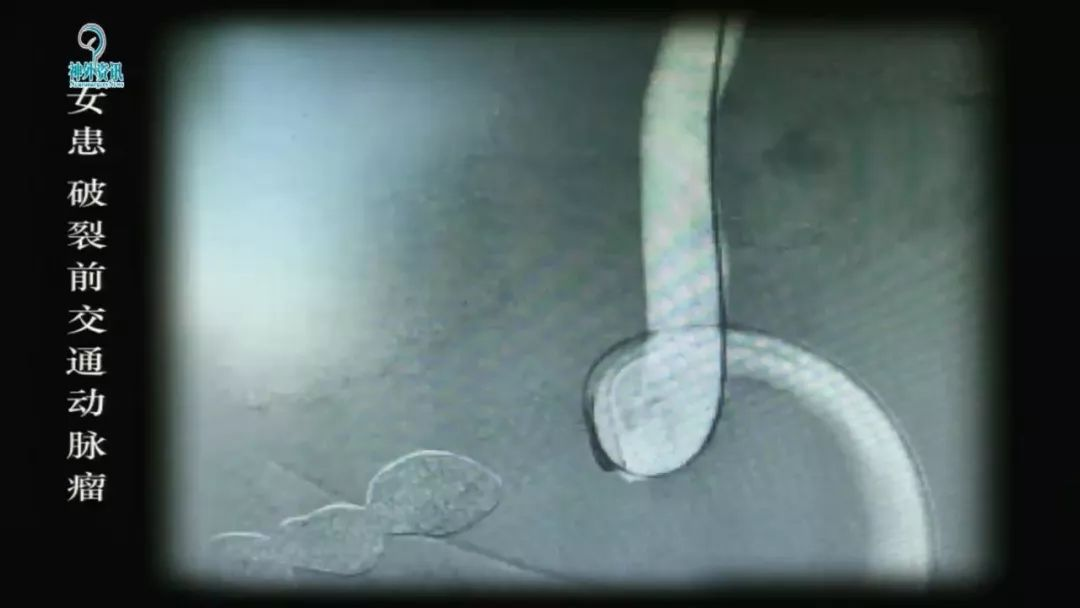

王智教授:从复合型医生的角度看待脑动脉瘤治疗的选择